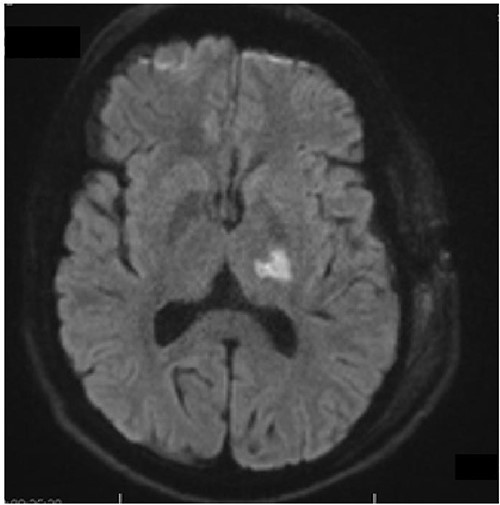

A 40-year-old man subjected to the outpatient care of our hospital for many years with the diagnosis of temporal epilepsy with complex partial seizures. After a long period free of seizures came in 2019 to a recurrence with episodes of focal epileptic seizures. The brain imaging with cranial magnetic resonance tomography (MRT) revealed a new lesion on the left hippocampus. The patient underwent regularly follow-ups in our outpatient clinic and the lesion has been shown stable until the last brain imaging in May 2022. The lesion has been changed morphologically and presented larger in size, with an increase in contrast enhancement. The lesion has appeared with a total mass of 8 × 14 × 15 mm, hypointense, surrounded by a peripheral hyperintense area, in the Flair sequence, Fig. 1. At that moment the patient complained intermittent dizziness and headache. He was otherwise alert, oriented with glasgow coma scale (GCS) 15/15. There was any cranial nerve palsy or neurological deficit of the extremities. The gait presented smooth and coordinate.

Flair sequence showing the lesion in the left amygdala as hypointense with surrounding hyperintense edema (links). T2-weighted imaging presenting the lesion hyperintense in the left amygdala (right).